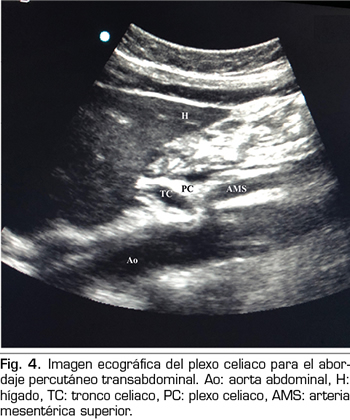

En los últimos años la ecografía ha ido ganando terreno a la fluoroscopia y al TAC en el manejo intervencionista del dolor. El primero en describir la técnica sobre el plexo celiaco fue Bhatnagar (31), pudiendo ser realizada percutáneamente en la cabecera del paciente y en decúbito supino, lo que da mayor comodidad tanto para el paciente como para el médico. Sin embargo, todavía no existen ensayos controlados y aleatorizados que comparen la neurólisis ecográfica abdominal del plexo celiaco frente al tratamiento sistémico opioide. La técnica se realiza utilizando una sonda convex (2-5 MHz), colocada inicialmente justo por debajo de la apófisis xifoides en el plano transversal, para identificar estructuras como hígado, estómago, intestino, venas portales, cava y aorta. Con la ayuda del Doppler, escaneamos caudalmente para identificar la bifurcación del tronco celiaco en las arterias hepática y esplénica, y más distalmente en la arteria mesentérica superior. Es entonces cuando giramos el transductor en el plano longitudinal, visualizando en la misma imagen la bifurcación de la aorta en el tronco celiaco y en la arteria mesentérica superior con el plexo celiaco rodeando estas estructuras. El  abordaje se realiza en plano, transabdominal, atravesando el hígado o el estómago, siempre y cuando no haya grandes vasos interfiriendo el recorrido de la aguja (Figura 4).